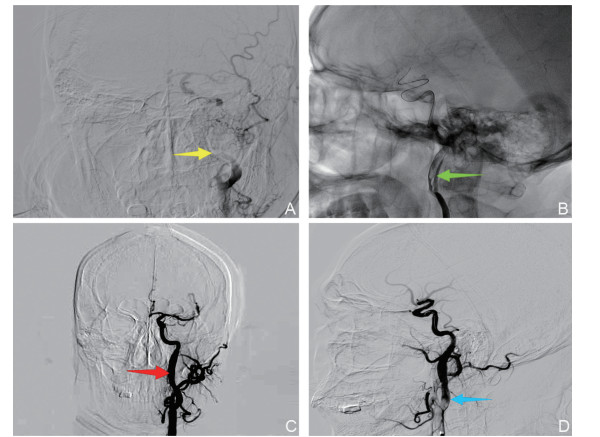

Association between the ratio of non-high-density lipoprotein cholesterol to high-density lipoprotein cholesterol ratio and severe intracranial/extracranial atherosclerotic stenosis

CHEN Ling, LYU Daping, YAO Ming, WANG Yongquan, WANG Ling

2025, 23(9): 1484-1487. doi: 10.16766/j.cnki.issn.1674-4152.004160

326 5

Abstract:

Objective  To investigate the correlation between the non-high-density lipoprotein cholesterol to high-density lipoprotein cholesterol ratio (NHHR) and severe atherosclerotic stenosis of intracranial/extracranial arteries. The study also seeks to provide a basis for the early screening of high-risk populations with severe intracranial/extracranial artery stenosis.  Methods  The present study is based on a cohort of 286 patients who underwent DSA examination in the Department of Neurology of the North District of the First Affiliated Hospital of Anhui Medical University from September 2018 to December 2024. The subjects were divided into two groups, namely the severe stenosis group (stenosis≥70% or occlusion, 197 cases) and the non-severe stenosis group (no stenosis or stenosis < 70%, 89 cases), according to the degree of stenosis. Clinical data and lipid profiles (total cholesterol and high-density lipoprotein cholesterol) were collected, and the NHHR was calculated. Multivariate logistic regression analysis was utilized to assess the independent association between NHHR and severe stenosis. Restricted cubic splines were used to analyze the nonlinear relationship between NHHR and the risk of stenosis. A stratified analysis was conducted in order to test the heterogeneity of the association.  Results  NHHR has been identified as an independent risk factor for severe atherosclerotic stenosis in intracranial and extracranial arteries (OR=1.141, P < 0.05). Subgroup analysis demonstrated consistent associations across different populations, with notably stronger effects observed in individuals aged 58-69 years (OR=1.474) and in patients with concurrent stenosis of both intracranial and extracranial arteries (OR=10.122, P < 0.05).  Conclusion  NHHR serves as a valuable indicator for predicting or evaluating severe atherosclerotic stenosis, particularly in the 58-69 age group and patients with concurrent stenosis of both intracranial and extracranial arteries.